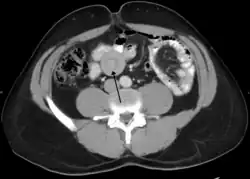

Tomografia komputerowa jest przydatnym badaniem w ocenie niedrożności jelit, szczególnie w zadzierzgnięciu, powikłań naczyniowych w przebiegu niedokrwienia i uwięźniętej przepukliny u osób otyłych[21].